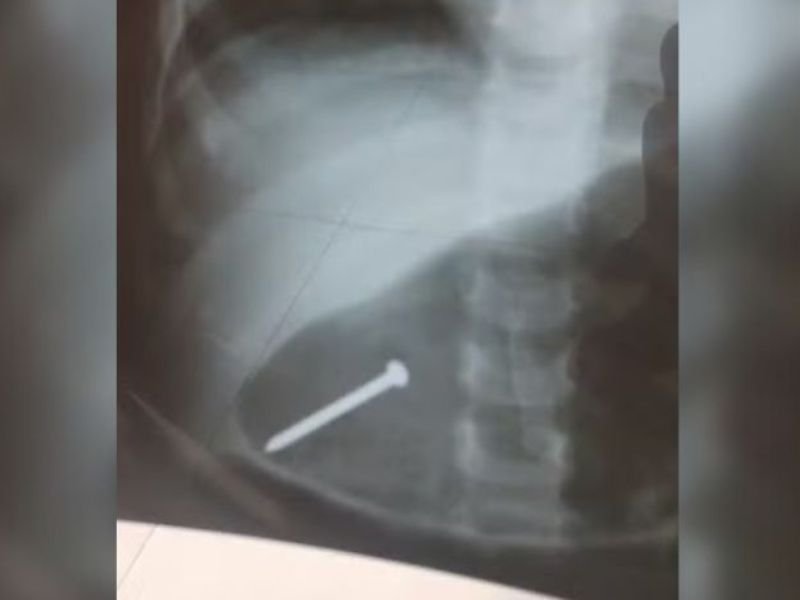

Brasil – Ums bebê de 1 ano e seis meses teve que ser internada após engolir um prego enquanto brincava dentro de casa, em Breves, no interior do Pará. O objeto no estômago da criança foi registrado por meio de um raio-x.

Até o momento, a Secretaria de Súde não divulgou o estado da criança. Familiares informaram que a bebê foi transferida par aum hospital em Belém, onde deve passar por uma endoscopia ou cirurgia para a retirada do prego.

A família passou a desconfiar de que isso tivesse ocorrido quando a menina começou a demonstrar que estava engasgada. Ele segue internada, aguardando o procedimento para tirar o prego do seu estômago.